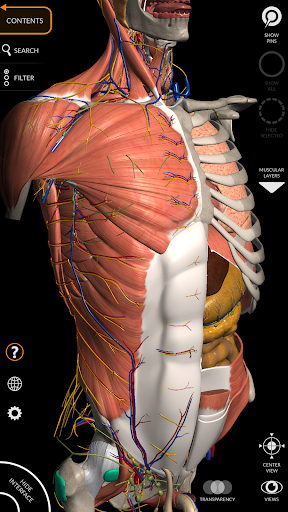

يتيح لك "Anatomy 3D Atlas" دراسة التشريح البشري بطريقة سهلة وتفاعلية.

من خلال واجهة بسيطة وبديهية، من الممكن ملاحظة كل بنية تشريحية من أي زاوية.

تتميز النماذج التشريحية ثلاثية الأبعاد بتفاصيل خاصة ودقة تصل إلى 4K.

يسهل التقسيم حسب المناطق والمناظر المحددة مسبقًا مراقبة ودراسة الأجزاء الفردية أو مجموعات الأنظمة والعلاقات بين الأعضاء المختلفة.

نماذج تشريحية ثلاثية الأبعاد

• الجهاز العضلي الهيكلي

• تصور العضلات من خلال مستويات الطبقات من الطبقات السطحية إلى الأعمق